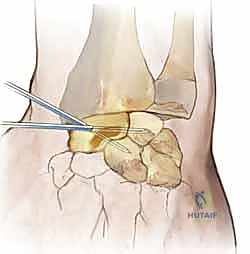

3. Creation of the Dorsal Capsular Flap

Now we focus on the dorsal capsule itself, which will form the basis of our capsulodesis.

• Flap Design: We need to create a robust, rectangular capsular flap. The dimensions are critical: approximately 25 mm long and 10 mm wide.

• Proximal Incision: We make a transverse capsular incision just proximal to the vascular dorsal carpal arch. This arch typically runs transversely across the dorsal aspect of the carpus. By staying proximal to it, we ensure the blood supply to our flap is preserved.

• Flap Elevation: Using a small periosteal elevator and careful sharp dissection with a #15 blade, we elevate the tissue in a distal-to-proximal direction. The key is to keep the flap thick and full-thickness, incorporating all layers of the dorsal capsule. We meticulously dissect it off the underlying carpal bones (scaphoid, lunate, capitate).